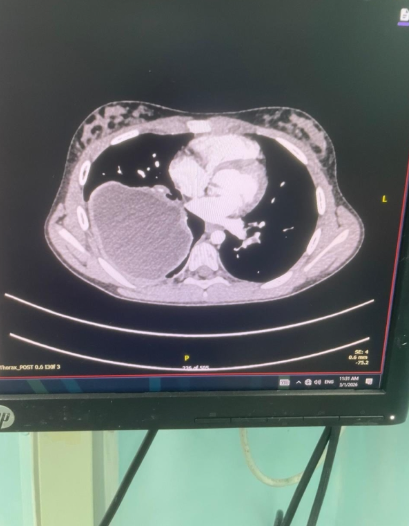

ععمان جو - أجرى فريق طبي متخصص من قسم جراحة الأطفال في مستشفى الملكة رانيا العبدالله للأطفال، برئاسة العقيد الطبيب وسيم المفلح، عمليتين جراحيتين لطفلتين كانتا تعانيان من وجود أكياس كلبيّة على الرئتين، بإستخدام المنظار الجراحي دون الحاجة إلى إجراء الجراحة التقليدية، من خلال ثقوب صغيرة في الصدر. وتُعد هذه العملية الأولى من نوعها على مستوى الخدمات الطبية الملكية.

وقال مستشار جراحة الأطفال العقيد الطبيب وسيم المفلح إن إستخدام المنظار الجراحي في مثل هذه الحالات لدى الأطفال يُعد تطوراً نوعياً ومميزاً على مستوى قسم جراحة الأطفال، لما يحققه من نتائج علاجية أفضل ويسهم في تقليل فترة الشفاء، والابتعاد عن الجراحة التقليدية وما قد يرافقها من مضاعفات، مشيراً إلى أن قسم جراحة الأطفال يسعى باستمرار إلى تطوير إستخدام تقنيات المنظار الجراحي في مختلف الحالات لمواكبة التطور الطبي في جراحة الأطفال والمسالك البولية للأطفال على مستوى المنطقة والعالم.